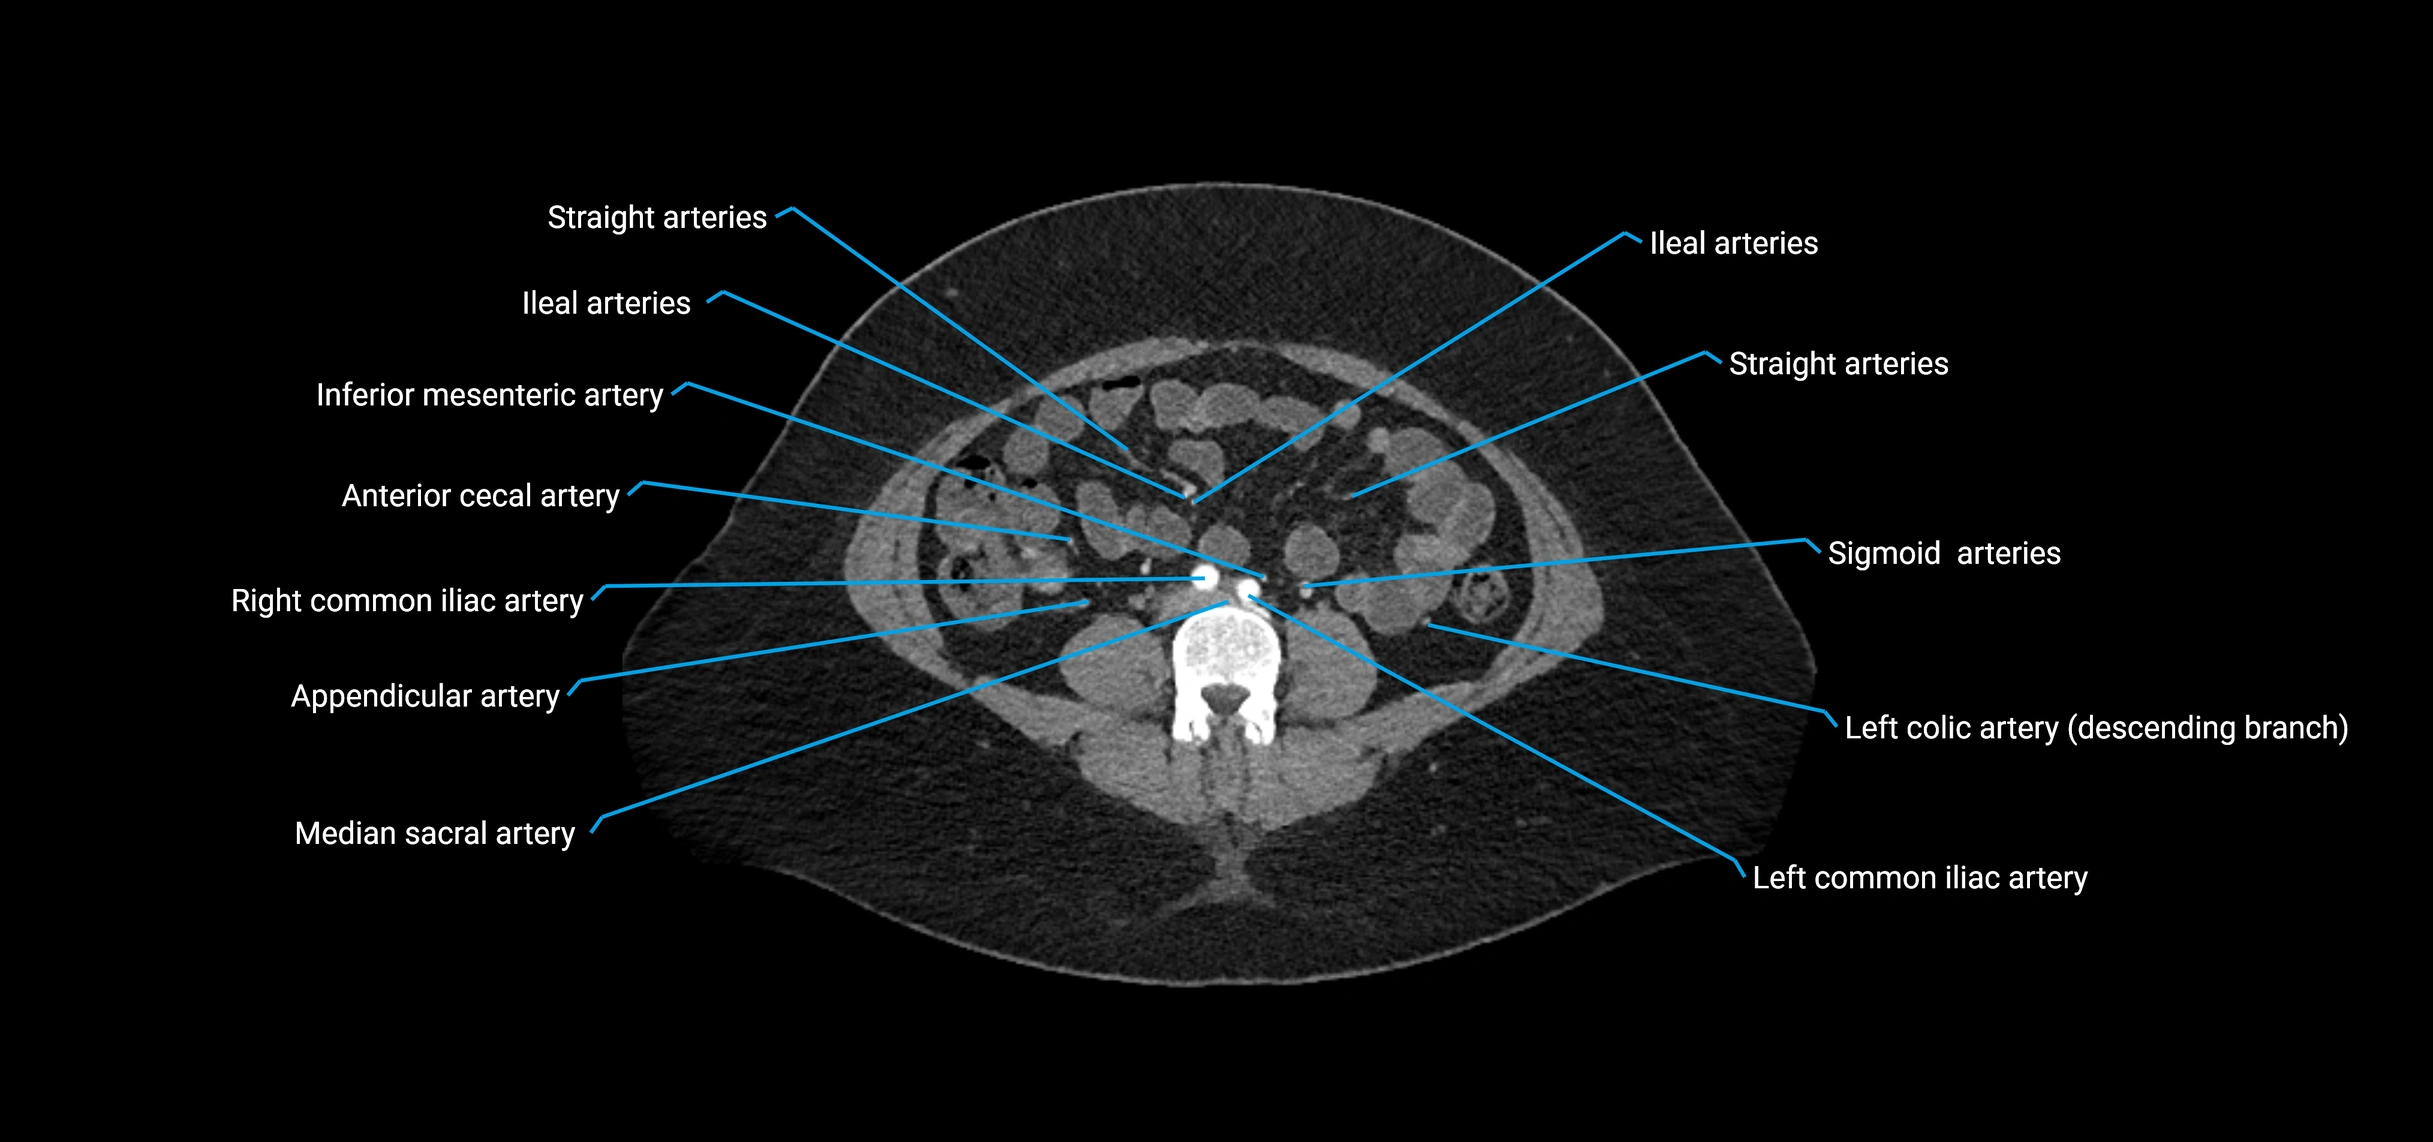

• Parietal branches: inferior phrenic arteries, lumbar arteries, median sacral artery

• Terminal branches: right and left common iliac arteries

Contrast-enhanced CT (CTA):

• Gold standard for abdominal aortic imaging

• Provides excellent detail of lumen, wall, aneurysm, thrombus, and branch vessels

• Multiplanar and 3D reconstructions help in aneurysm measurement, stent graft planning, and dissection evaluation